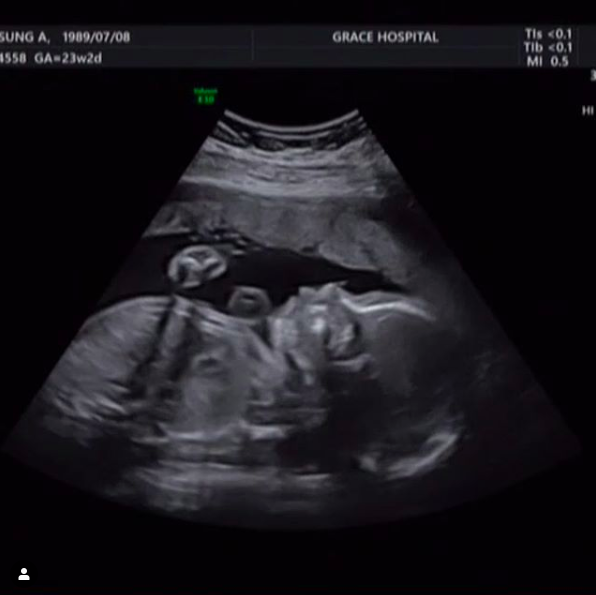

손성아는 1일 자신의 SNS에 "안녕하세요 윤축복이에요. 저 3월에 엄마돼요. 셀레는 마음으로 기다리고 있어요 헤헤. 이제 27주, 쥐띠맘, 극성맘예약, 임밍아웃"이라고 임신 사실을 공개했다.

이와 함께 초음파 사진을 게재, 팬들과 지인들의 축하를 받고 있다.